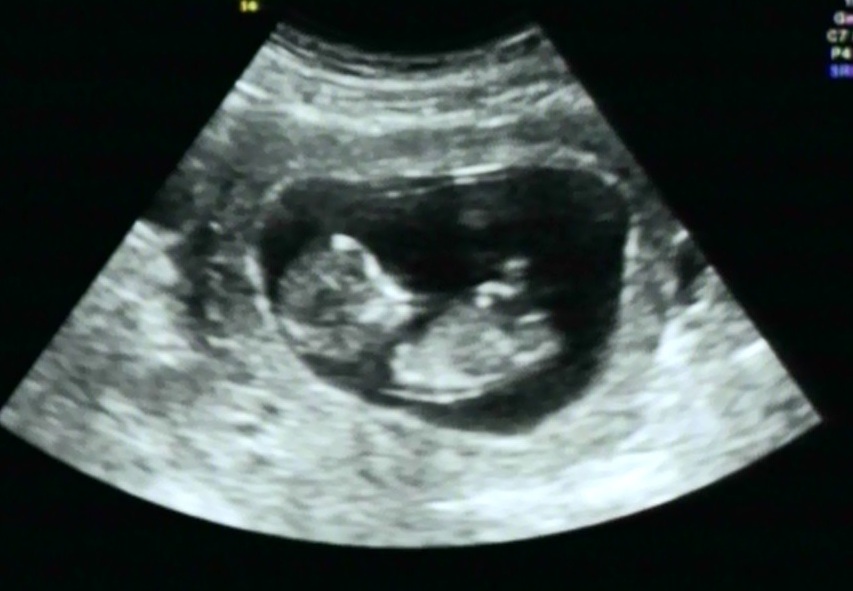

We've had 2 boys so we are hoping for the girl, can anyone tell me if the nub looks pink or blue?

Attachment 12991

Possibly pink

Also new to this, but my guess is pink too...

Still pretty early...but looks girly :)